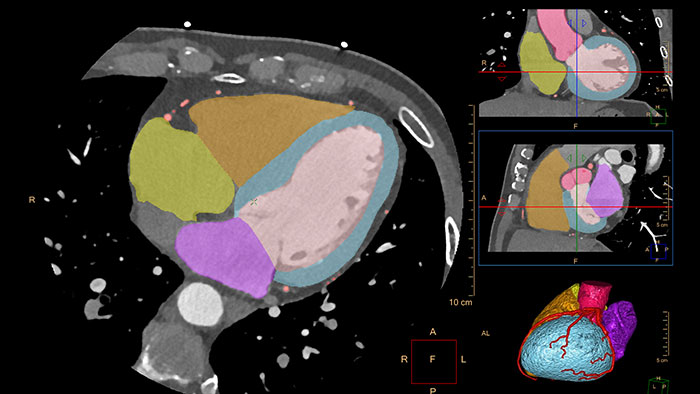

Comprehensive Cardiac Analysis (CCA)

CT Comprehensive Cardiac Analysis (CCA)

Comprehensive cardiac analysis

Designed to assist the user in viewing, analyzing and quantifying dedicated Cardiac CT Angiograms, mainly for coronary arteries analysis on Coronaries CT Angiogram (CCTA) data.

Benefits

• Cardiac function measurements based on automatic 3D model-based whole-heart segmentation.

• Automatic extraction and visualization of the coronary tree.

• The user can edit and modify the segmentation and the derived parameters.